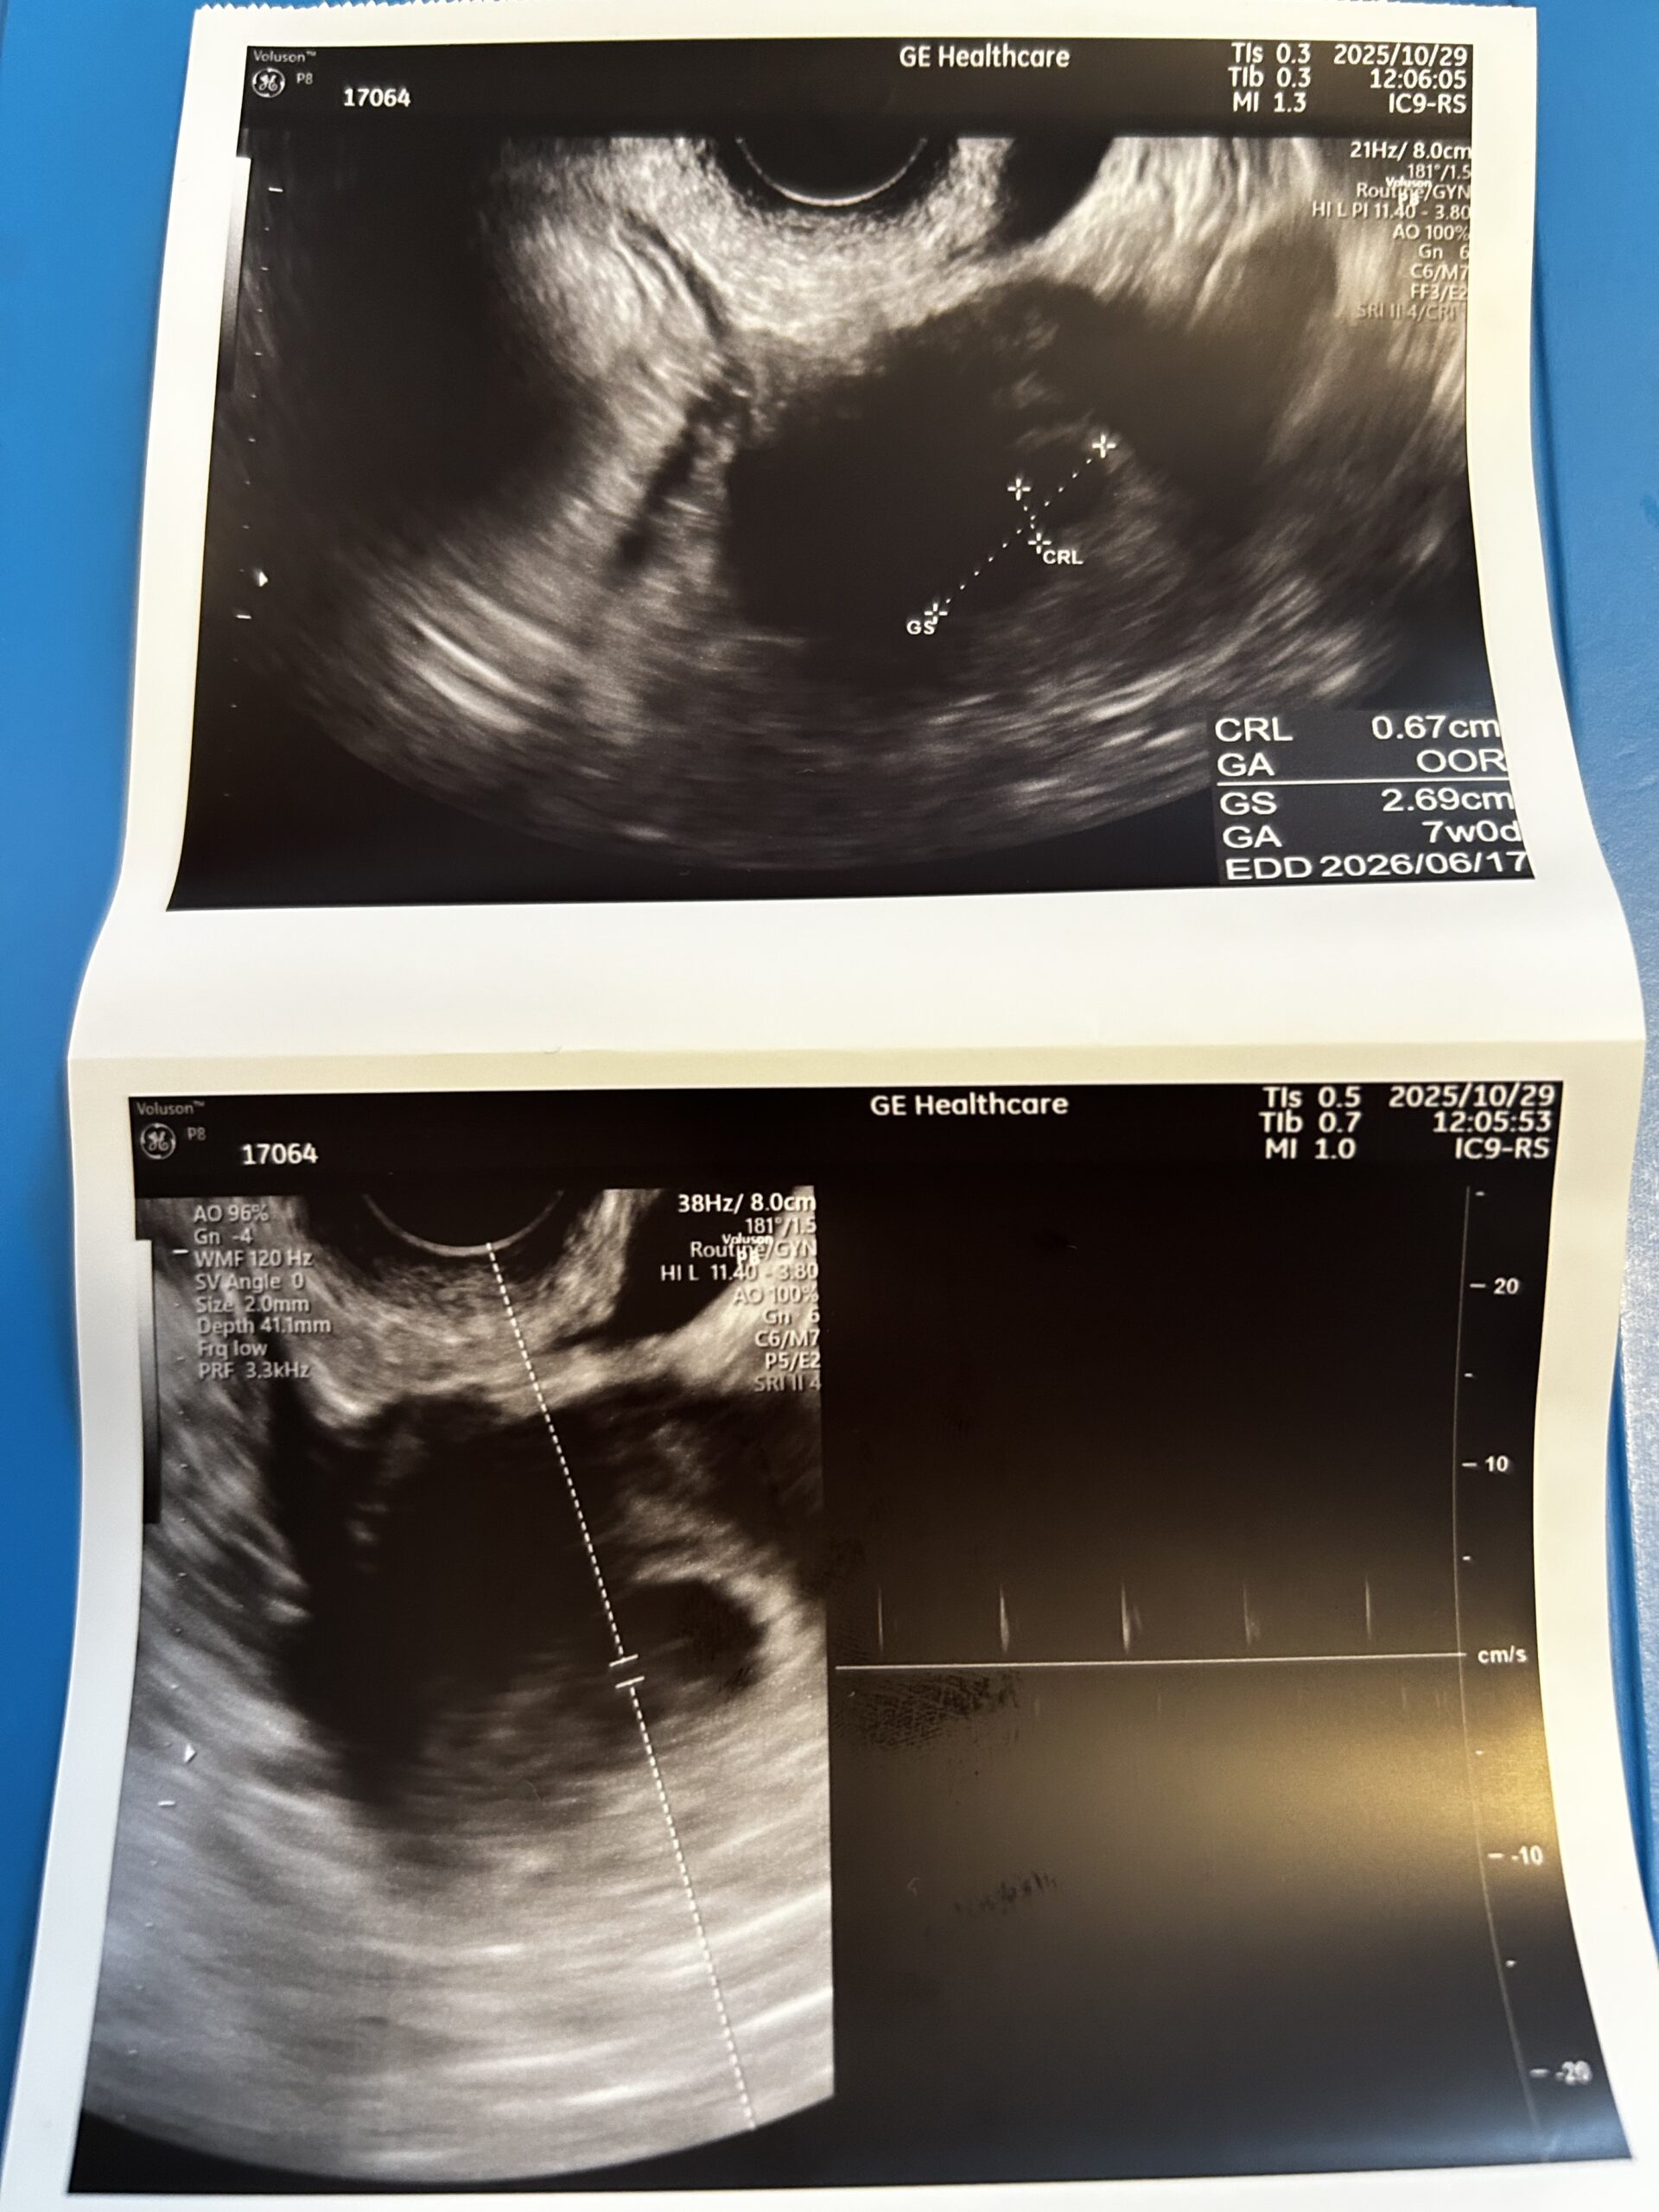

20歳だったあなたは薬学部を卒業し、立派に天国で薬剤師として働いているとこでしょう。私は、昨年2回自然妊娠し、そして2回流産しました。 きっと哲が全てを見守って、天国でその子たちと過ごしてくれてい